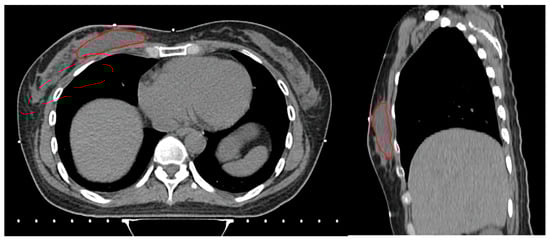

The dimensions of the surgical specimen, including width (cm), depth (cm), and height (cm), as well as the width and depth (cm) of the excised skin, were obtained from the gross pathology report. Skin depth and width were measured from the surgical pathology specimen. Skin depth was defined as the vertical thickness from the epidermis to the dermis and skin width as the lateral dimension of the excised skin. Measurements were taken from a representative area of the specimen using standardized calipers. The specimen volume (cc) was calculated by multiplying the width, depth, and height of the surgical specimen. Breast volume (cc) and surgical cavity (cc) were calculated by segmenting each axial slice of simulation computed tomography (CT) according to the RTOG guidelines [15] using MIM (MIM Software Inc., Cleveland, OH, USA). Surgical cavity was defined as a localized fluid attenuation, separate from the surrounding breast parenchyma on a CT image (Figure 1).

Figure 1. Segmentation of surgical cavity shown in axial (left) and sagittal (right) views of simulation CT.